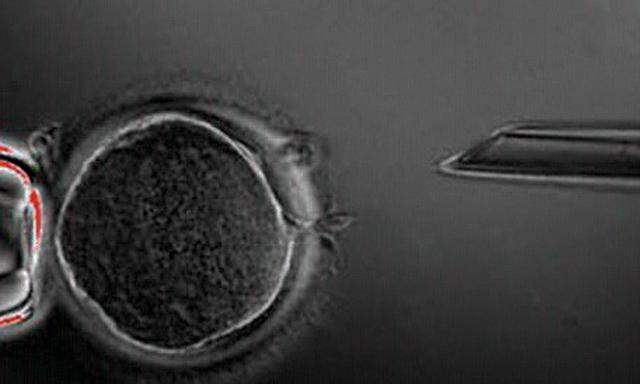

Denn, ja, es ist dem Team um Manuel Serranol geglückt, in genetisch veränderten Mäusen pluripotente Zellen zu produzieren. Das sind Zellen, aus denen alle Zelltypen des Körpers werden können, die ihre Differenzierung verloren haben, die also eine wichtige Eigenschaft embryonaler Stammzellen haben. Aber dass sie solche sind, das behaupten auch die Forscher nicht. Sie hätten durch „reprogramming in vivo“ zweierlei erhalten, sagt der Titel ihres Artikels in Nature (11.9.): induzierte pluripotente Zellen (iPS-Zellen) und Teratome.

Das Neue an der Arbeit ist jedenfalls, dass die Reprogrammierung, die bisher in vitro gelungen ist, nun auch in vivo geglückt ist – über die gleichen vier Gene, die nun in den Mäusen über eine in deren Trinkwasser gemischte Chemikalie angeschaltet werden können. Ein seltsames Ergebnis: Die in vivo entstandenen iPS sind laut Nature ursprünglicher, „mehr totipotent“, als die in vitro produzierten Zellen. Man sieht: Hier ist noch viel unverstanden. tk